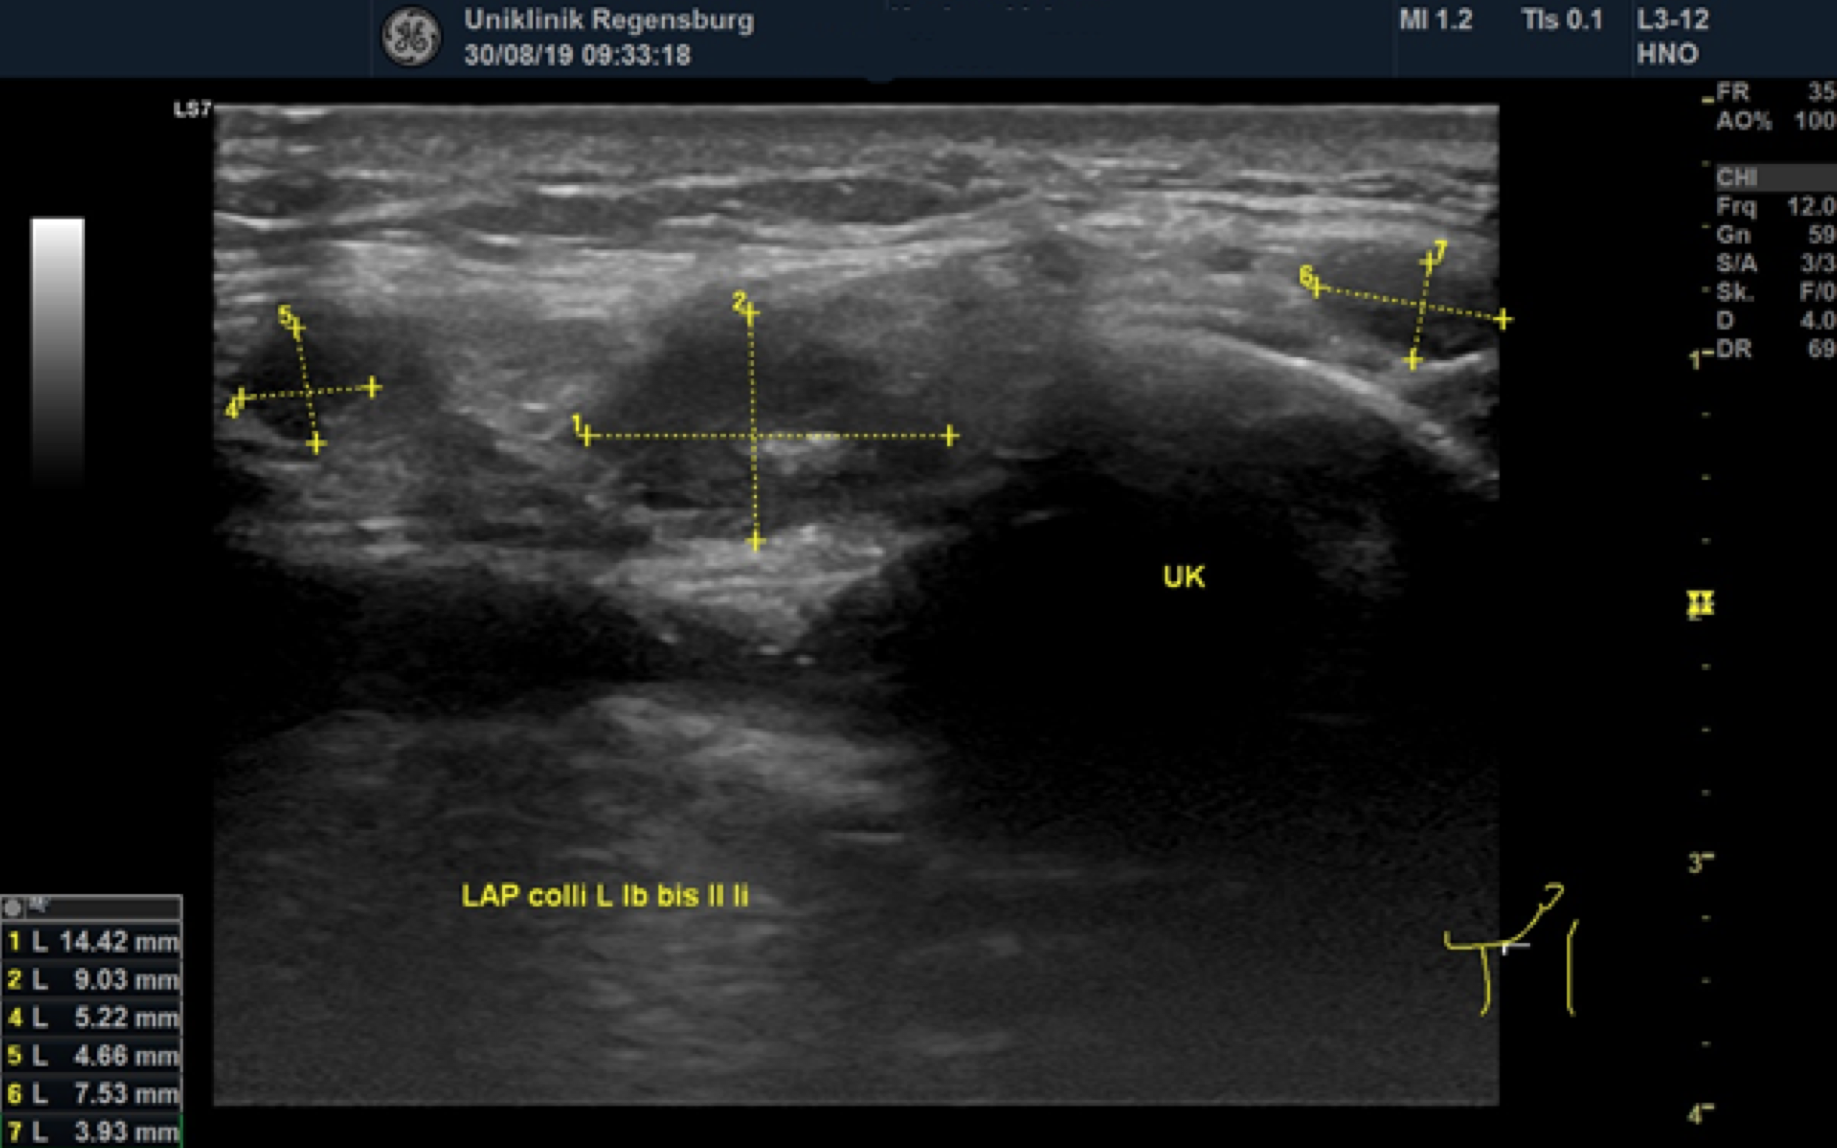

Preoperative ultrasonographic findings showed an oval hypoechoic inhomogeneous mass, approximately 4 x 3 x 1.5 cm in levels III to IV of the left side of the neck below the sternocleidomastoid muscle. (Fig. 1) The mass was partly indistinct to the adjacent tissue and demonstrated peripheral perfusion with no central vascularity. (Fig. 2) The surrounding soft tissues appeared oedematous and thickened. (Fig. 1 – 2)

Figure 1. Hypoechoic inhomogeneous mass partly indistinct from the adjacent tissue in Levels III to IV of the left neck; ACC = Common carotid artery; MSCM = sternocleidomastoid muscle.